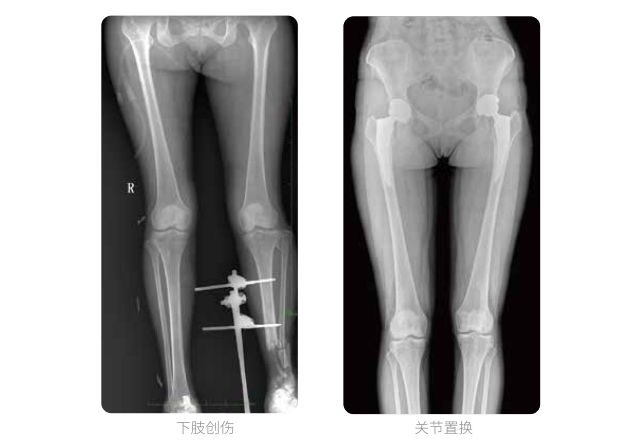

一次曝光 讓較長髓內釘細節畢現

雙下肢臨床影像

髓內釘手術是骨科、手足外科中常見的微創型手術方式,患者隨訪時需拍攝置入在股骨、肱骨處的較長髓內釘。PLX8600視野拍攝,能夠出色解決醫生需多次攝影再拼接的痛點。一次成像雙下肢,即拍即得,高效率,無需拼接。工作站軟件自帶的測量功能方便醫生讀取雙下肢長度數據,助力準確診斷。

動態DR所具備的全脊柱、全下肢全景成像技術檢查,能夠更加清晰的顯示患者病情變化情況,對骨科疾病患者的全脊柱、全下肢病變情況圖像展示更加具有完整性,對患者在自然狀態下的應力情況展示較為全面,有助于骨科疾病患者臨床診斷效果的提升,對患者臨床治療方案的科學制定有著積極的作用。